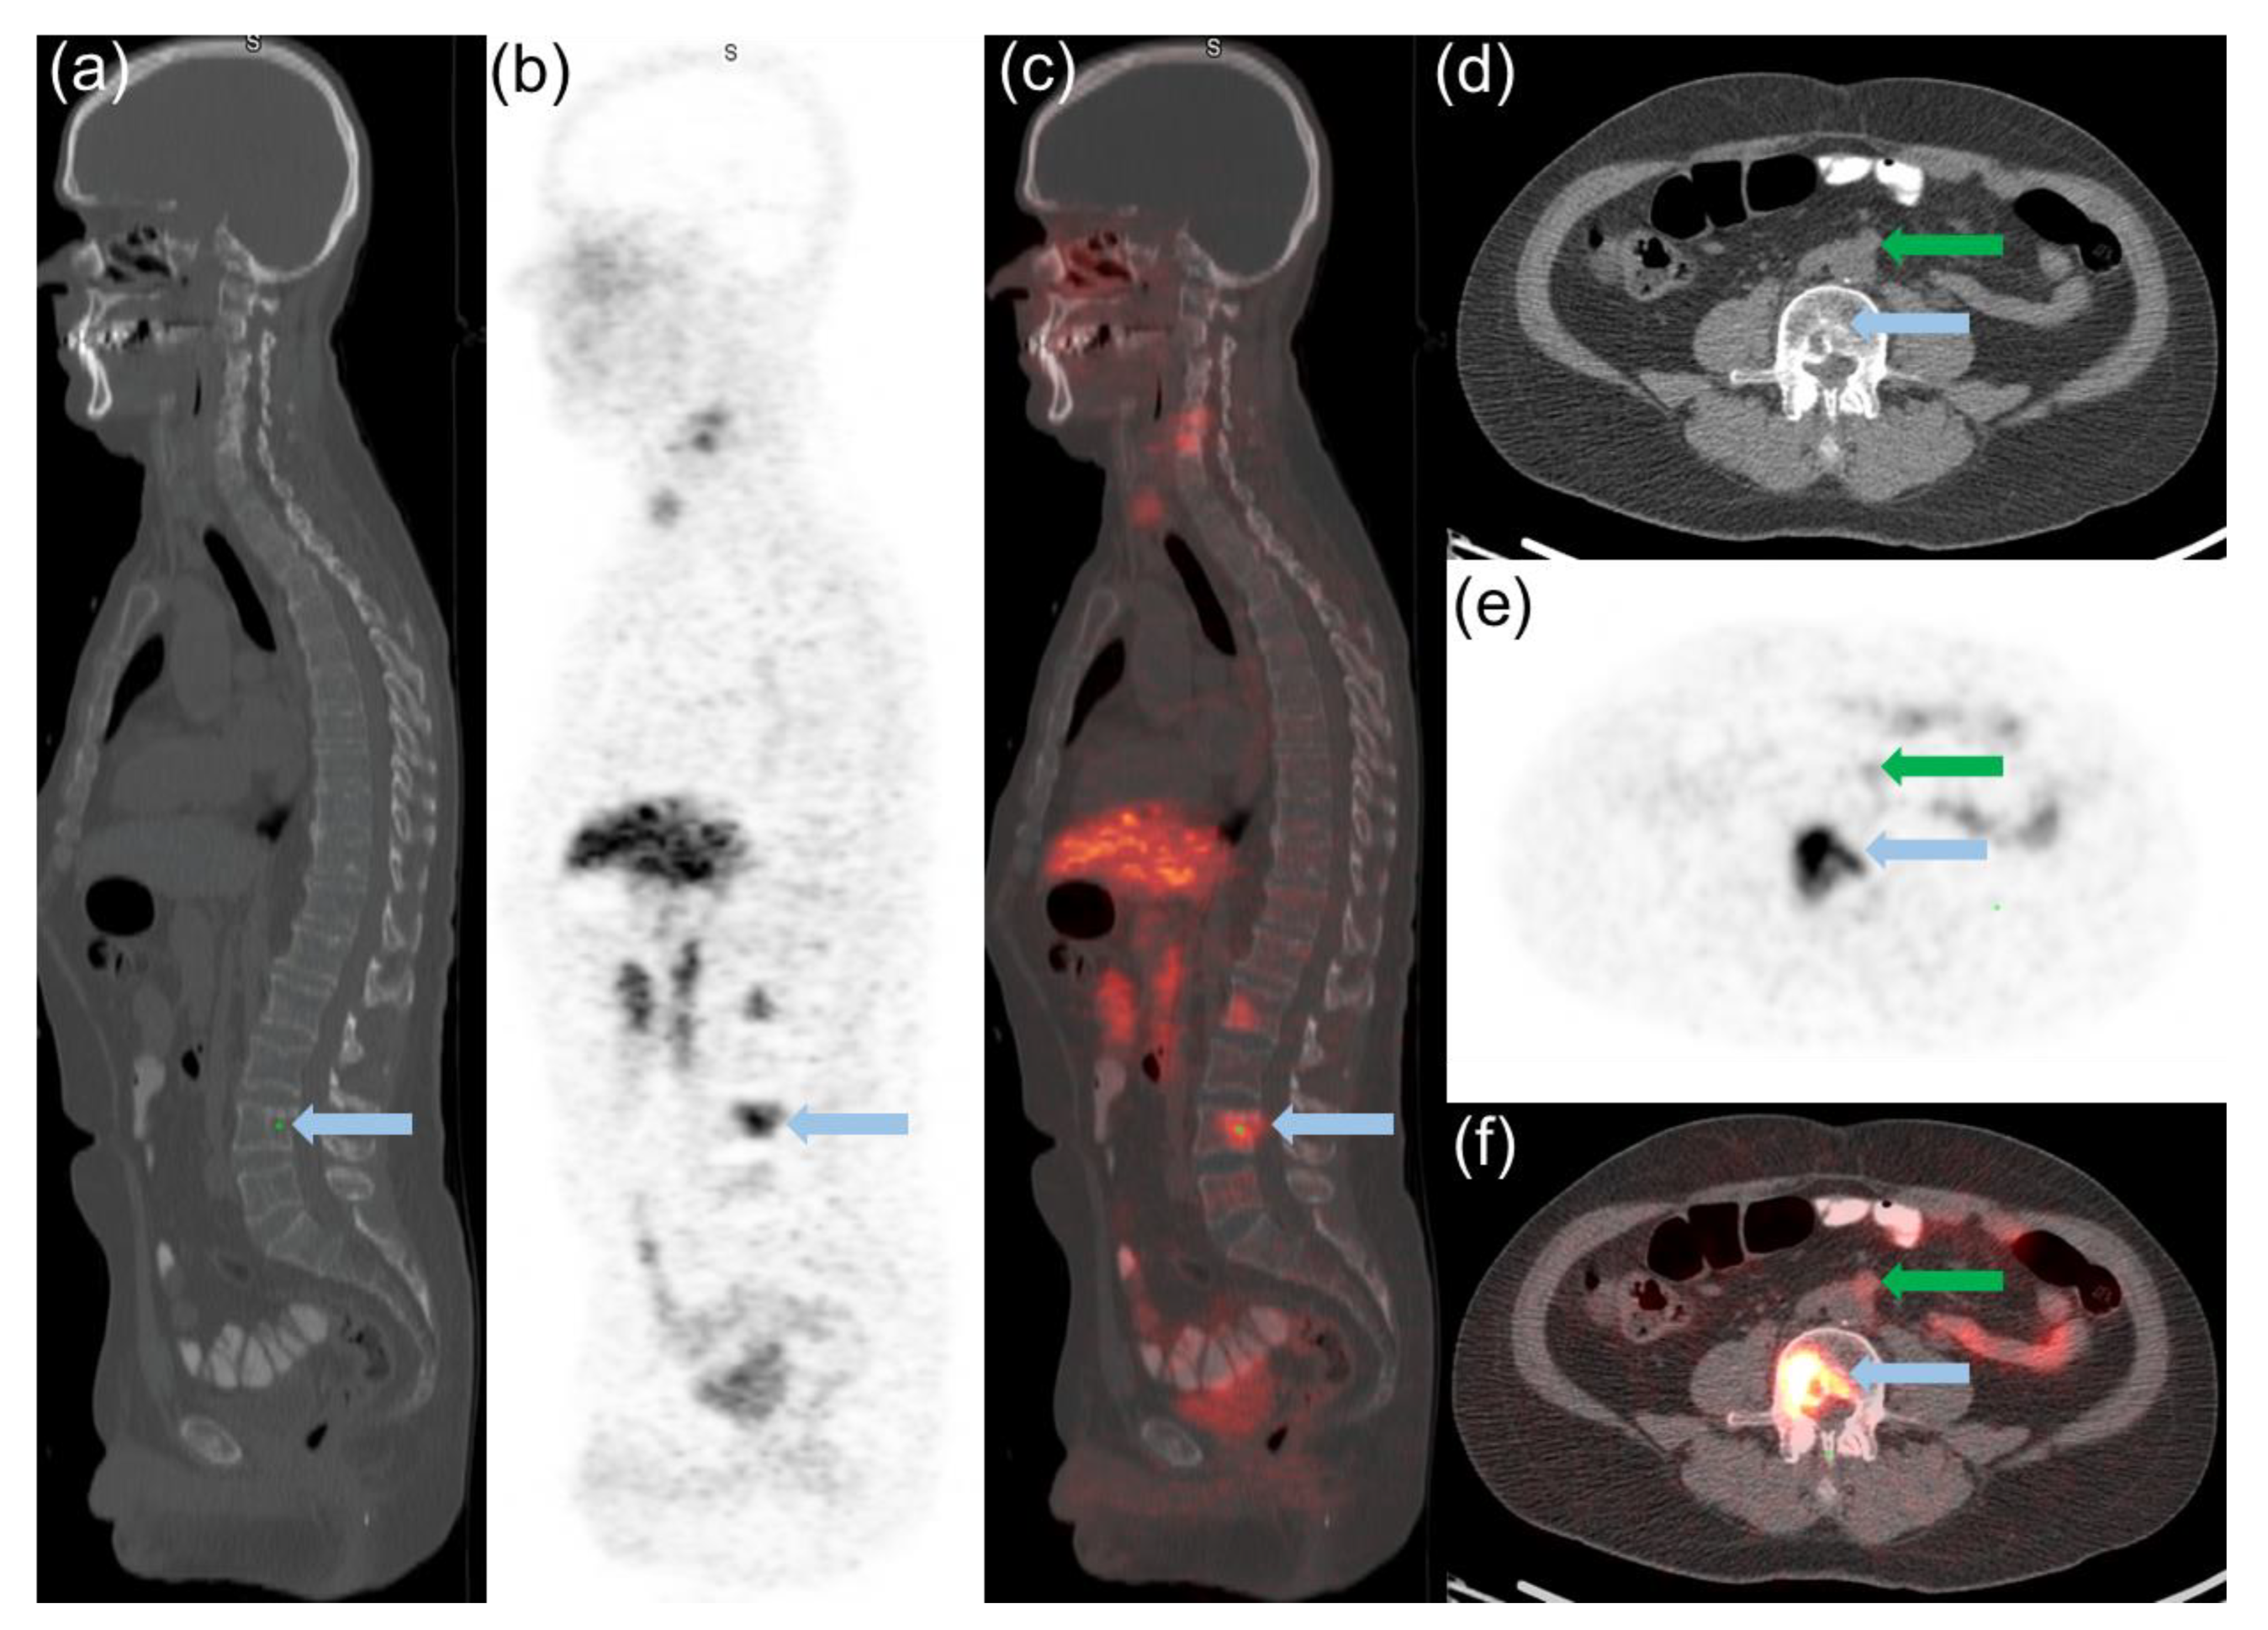

Semiquantitative PET and Visual Analysis